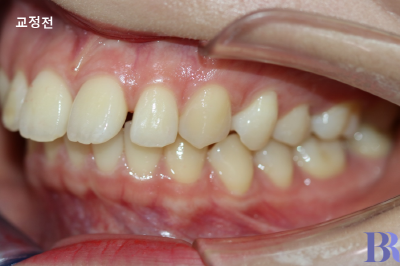

윗니와 아랫니 앞뒤차이가

심하게 나는 것을 볼수 있네요.

윗니가 아랫니에 비해

현저히 앞으로 나와 있거나,

입술 돌출이 중간 정도로

심하지 않은 경우입니다.